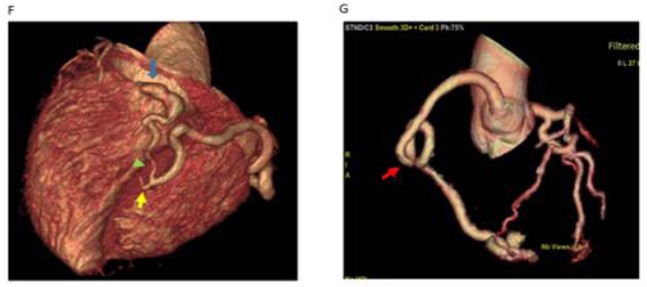

Coronary cameral fistula in a 57-year-old female patient presented with chest pain. Volume-rendered CT images obtained at different levels show a right coronary artery coursing in the atrioventricular groove with a subsequent bifurcation forming the posterior descending artery (PDA) (yellow arrow in f) and posterior left ventricular branch (PLV) (green arrow in f). PLV is draining as coronary cameral fistula into the left ventricle chamber (blue arrow in f). Note the tortuous course of the proximal segment of the right coronary artery (arrows in g).

Figure 2: